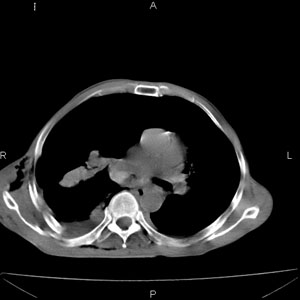

患者男,77岁,于3日前从树上摔下,头部查ct示蛛血,硬膜下出血,上腹部ct未见明显异常,右侧胸腔积液,左侧如常。肺部拍片示右侧肋骨多发骨折住院后今日来查肺部ct,我看到的是1。右侧胸腔血气胸并右肺上叶,中叶压缩性肺不张,2。右肺下叶肺挫伤并多发肋骨骨折,肌内及皮下积气3。左侧少量胸腔积液,我想请教的是3天前左侧胸腔里没有积液今天怎么出现了呢,是什么原因呢?请讨论。

右侧多发肋骨骨折,同侧液气胸